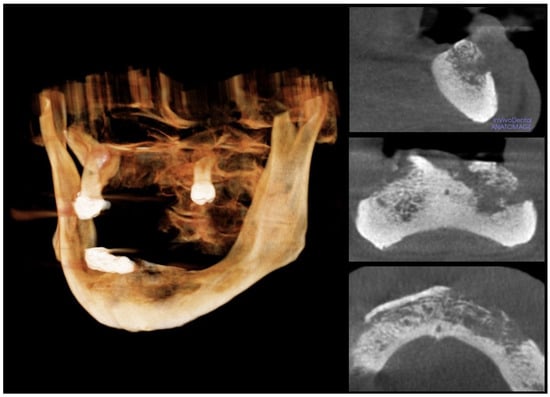

The first recorded scenario was ORN because the patient underwent radiotherapy in 2020. The oral surgeon formed the hypothesis of stage-III MRONJ because of the combined administration of denosumab, cortisol, and cemiplimab. Eventually, a hypothesis of the cutaneous SCC invading the mandible arose because of the lack of surgical resection of such a malignancy. The aim of the medical team was the histological examination of the ENB after the surgical excision under general anesthesia; thus, the patient underwent a panoramic radiogram, cone beam CT, and a visit by the consultant anesthesiologist. In addition, the patient discontinued denosumab after consulting with the oncologist. The patient received three cycles of antibiotic therapy; each cycle included 1 gr of ceftriaxone and 500 mg of metronidazole daily for a week; 15 days of wash-out occurred between consecutive cycles. However, the patient’s general health conditions worsened due to SARS-CoV-2 infection a few days before the excision, and the oncologist contraindicated the surgery in agreement with the anesthesiologists. Therefore, the oral surgeon performed the sequestrectomy of the ENB and the extractions of the lower teeth under local anesthesia and antibiotic prophylaxis; the histological examination of the ENB confirmed the hypothesis of MRONJ because the sample showed bony structures characterized by wide acellular necrotic regions, large and scalloped Haversian canals, and inflammatory infiltrate; the pathologists found basophilic bacterial colonies and inflammatory infiltrate composed of polymorphonuclear phagocytes, plasma cells, monocytes, and lymphocytes [12]. The wound showed partial healing a month after the surgery. The medical team continues to conduct monthly follow-ups for the patient; each visit includes the delivery of photobiomodulation (PBM) therapy as an adjuvant technique to manage the wound; the PBM protocol involves a diode laser with a wavelength of 810 nm in noncontact continuous wave mode to irradiate 1 W/cm2, for a total exposure time of 1200 s per session. The combination of PBM and cycles of antibiotics keeps the MRONJ lesion steady, and the oncological therapy prevents the growth of the SCC. In addition, the authors also delivered PBM to the labial ulcers and have suggested covering these lesions with Vaseline oil to alleviate the pain. Before drafting this manuscript, the last follow-up visit occurred in June 2024; the patient was alive and without symptoms.

Figure 4. Cone beam computed tomography. The cone beam computed tomography with 3-D reconstruction of the osteolytic area shows the sequestration of the necrotic bone.